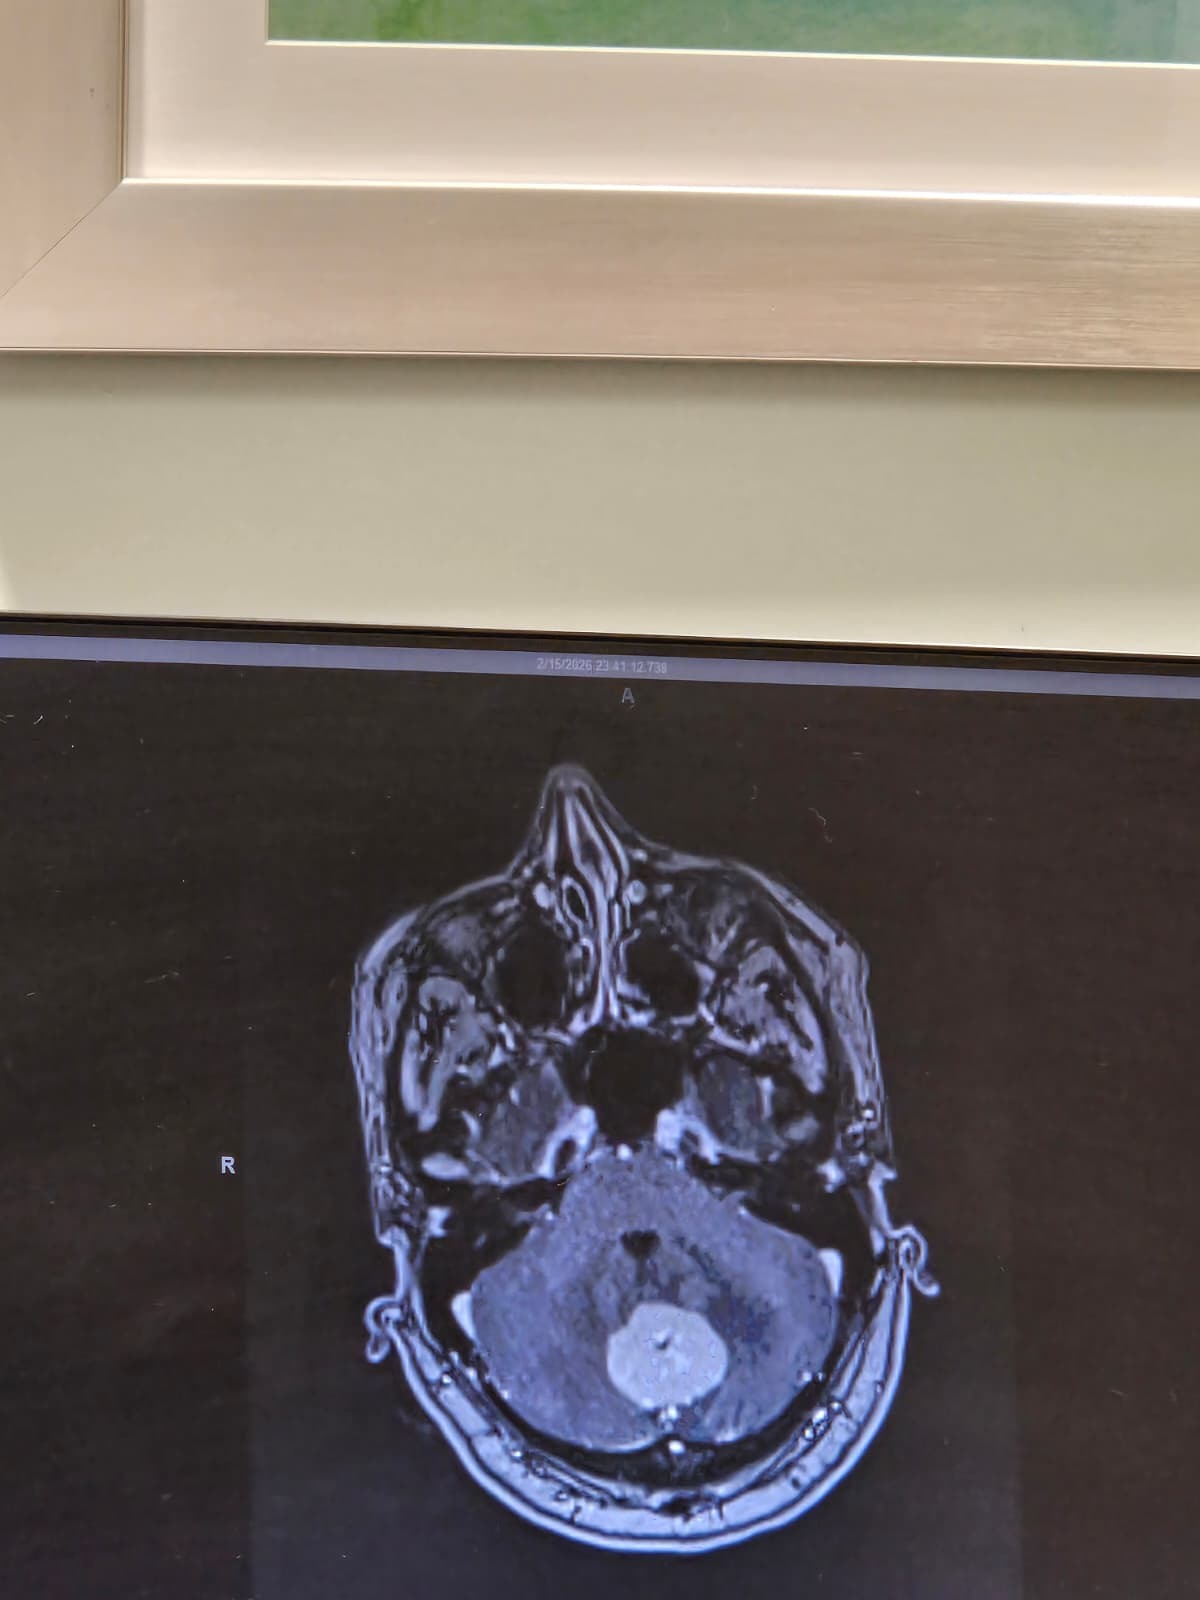

In October 2024, our world changed when my wife was diagnosed with triple-negative breast cancer, stage 3. She bravely faced months of chemotherapy, radiation, and surgery, and we were overjoyed when she reached full remission. For a brief moment, we believed everything was fine. But soon after, a severe headache and sudden vision loss sent us back to the hospital, where doctors discovered a 3.3 cm tumor in her cerebellum. She underwent emergency surgery to remove the tumor, followed by more radiation therapy. Just seven weeks after surgery, she suffered a brain convulsion and was rushed to the ER. Multiple tests confirmed that the cancer had spread throughout her brain fluid and spinal column tissues and membranes. She is still in the hospital, fighting for her life every day.